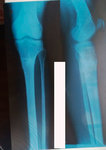

Дата снятия аппаратов - 15.02.2020

Срок сращения 92 дня.